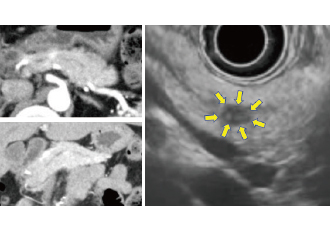

当科では進行がんの治療だけでなく、早期発見のための努力をしています。特に消化器系のがんに関しては、専門医が早期診断・検査にあたっており、CT、MRI、PET-CTなどの画像検査に加えて、上部消化管内視鏡検査、大腸内視鏡検査、内視鏡的逆行性胆管膵管造影(ERCP)、超音波内視鏡検査(EUS)を行います。

特に、膵がんの早期発見には特に力を入れており、膵腫瘍・膵のう胞専門外来を設置し、危険因子(糖尿病、がんの家族歴、膵のう胞など)のある患者様には積極的に超音波内視鏡による早期膵がんの検査をお勧めしています。

微小膵癌がEUSで描出される